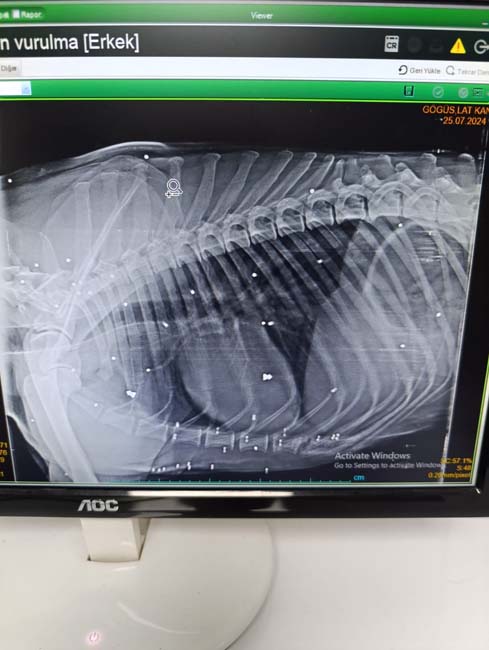

İddiaya göre, Almanya'dan Bartın'ın Kozcağız beldesine yıllık izne gelen 19 yaşındaki gurbetçi H.C.U., 22 Temmuz günü alkol aldıktan sonra Ateş isimli sokak köpeğini av tüfeğiyle başından vurdu. Silahtan çıkan kurşun, köpeğin burnunda delik açtı. Yaralanan köpeği fark eden vatandaşlar, sosyal medya üzerinden Zonguldak'taki hayvansever Seda Kaya'ya ulaşarak durumu anlattı. Kaya, köpeği Zonguldak'taki veteriner kliniğine getirdi. Burada ameliyata alınan köpeğin vücudundan çok sayıda kurşun çıktı. Hayvanın gözü de ampute edildi. Çıkarılan kurşun ise burnunda delik açtı.